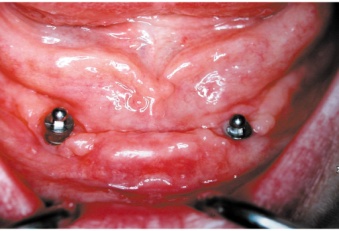

Kulové attachmenty

Bezzubá čelist je hlavní indikací pro ošetření pomocí implantátů. Zejména celkové zubní náhrady v dolní čelisti mají velice nízkou stabilitu a držení díky velkému úbytku kosti.

S pomocí zubních implantátů můžeme díky různým kotevním systémům (třmeny, kulové hlavy, Locatory) zajistit stabilitu a držení protézy nebo při použití většího počtu implantátů zhotovit pevné náhrady – můstky nalepené nebo našroubované na pevno na implantáty.

S těmito typy náhrad můžeme dosáhnout perfektní funkci, výbornou estetiku, fonetiku a současně zajistit u pacienta možnost dobré hygienickou péče a čištění, která je pro životnost implantátů velice důležitá.